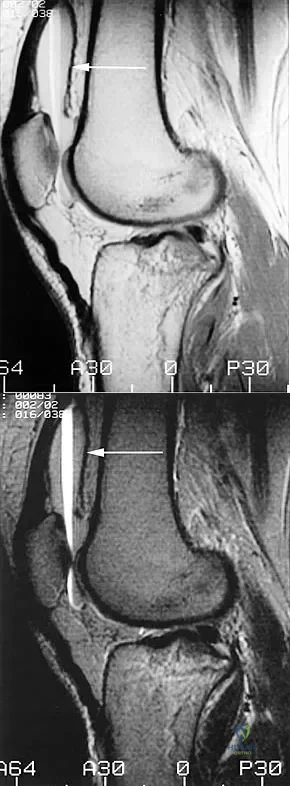

Figures 31a and 31b show the T1- and T2-weighted MRI scans of a patient's knee joint. What is the most likely diagnosis?

Explanation